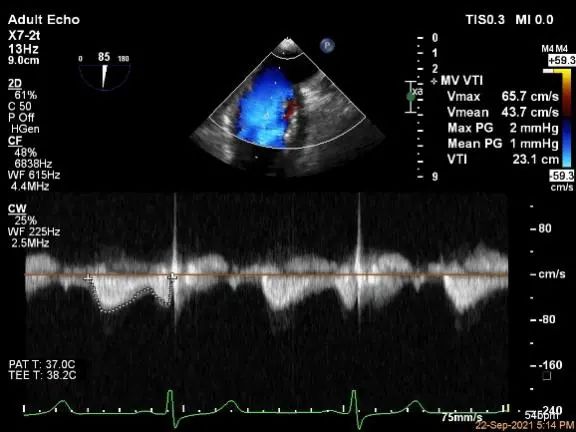

MVA:7.8cm²,平均跨瓣压差:1mmHg

房间隔穿刺点选择

穿刺高度:4.08cm

评估二尖瓣瓣口平均跨瓣压差:1mmHg

肺静脉血流频谱恢复正常